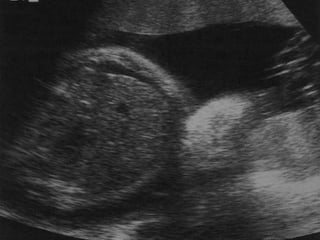

PRESENCIA DE DOS O MÁS DE LOS

SIGUIENTES HALLAZGOS:

•ASCITIS FETAL

•DERRAME PLEURAL

•DERRAME PERICÁRDICO

•EDEMA SUBCUTÁNEO (MAYOR A 5 MM)

•HIGROMA QUÍSTICO

•POLIHIDRAMNIOS (50-75%)

•ENGROSAMIENTO DE LA PLACENTA

(MAYOR A 6 CM)